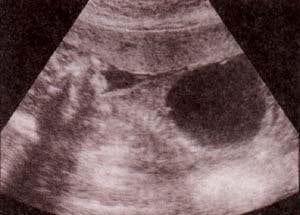

fig. 77. ectopia cordis. Corte transversal alto a nivel del abdomen. 30 semanas. se observa defecto de pared abdominal alto asociado a ectopia cordis. nótese el corazón insinuándose dentro del onfalocele se trata de una malformación que engloba 5 alteraciones.

fig. 78. imagen macroscópica del feto correspondiente a una pentalogía de cantrell. es evidente el defecto abdominal extenso, asociado a excencefalia y alteraciones de las extremidades la necropsia confirmó cardiopatía y defecto anterior del diafragma. |